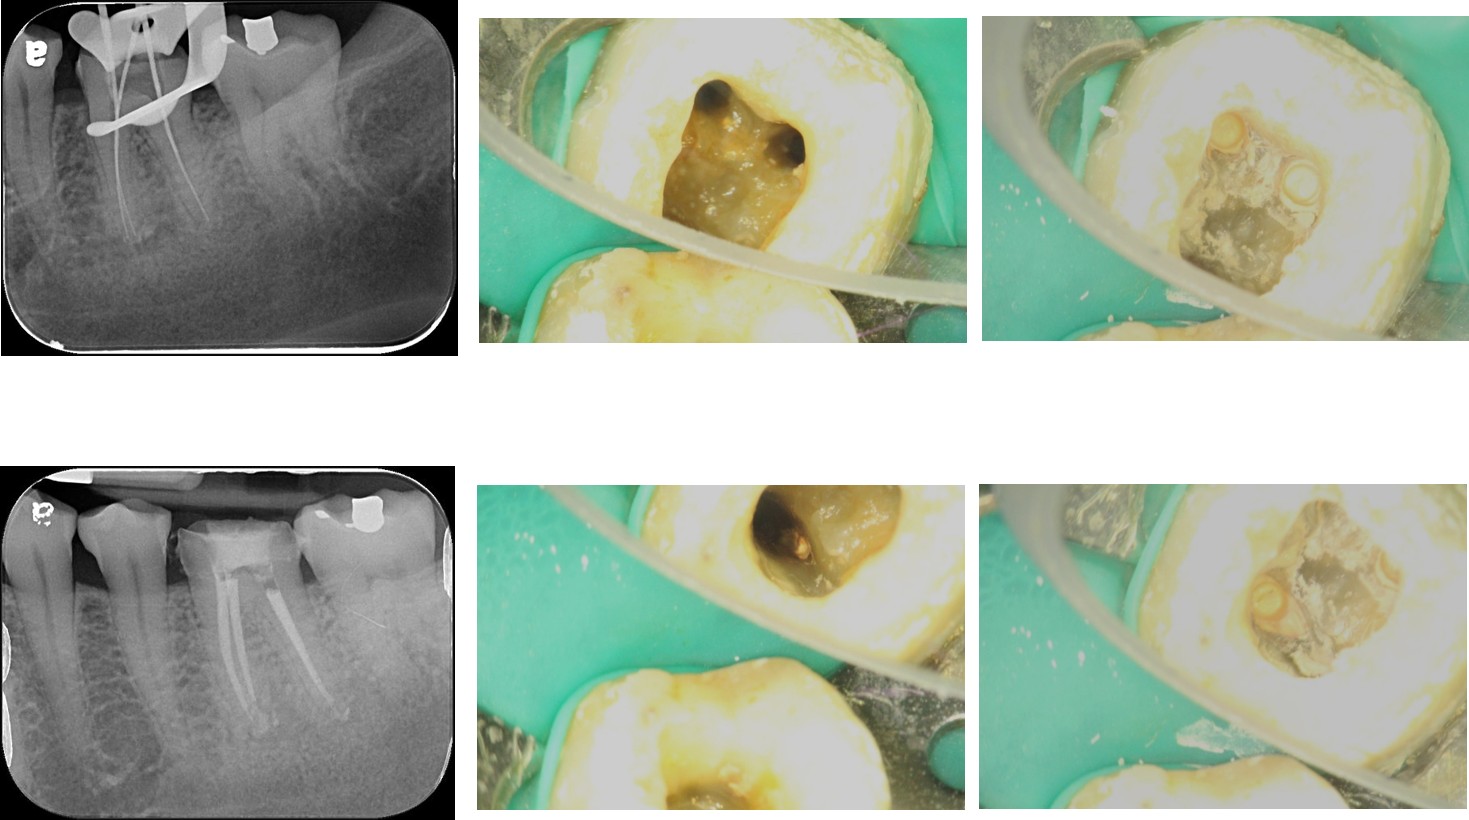

顯微根管治療-根管治療不完全-#36

治療前,根管治療不完全

根管重治療與充填

治療後,根管充填緻密

術前、術後比較